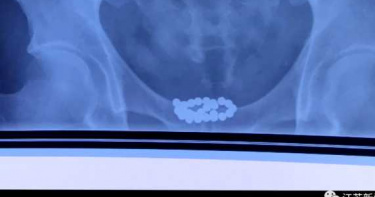

「29顆磁力珠」塞尿道!他忍10天狂噴血尿 醫一看嚇傻:都鈣化了

大陸陝西1名男子近日到醫院就診,指自己有血尿、頻尿等症狀,但他面對醫生問診時卻支支吾吾,經追問後才坦承,自己10天前把「磁力珠」塞進尿道,不久後開始出現不適,然而他害怕開刀,才會一拖再拖。醫生了解狀況後,決定透過微創手術將異物取出,赫見磁力珠留在人體時間過長,都已經鈣化了。《江蘇新聞》報導,家住陝西省西安市的男子近日突發奇想,竟將29顆玩具磁力珠塞進自己尿道,結果沒多久就開始出現不適,並陸續出現頻尿、尿道疼痛,甚至血尿等症狀,嚇得他趕緊到醫院檢查,然而一聽到必須開刀,他就害怕地打退堂鼓,強忍了10天實在疼痛難耐,只好硬著頭皮就醫。患者體內的磁力珠已鈣化。(圖/翻攝自江蘇新聞)由於病患對開刀有疑慮,因此主治醫師也相當貼心,改從尿道口進行微創手術取出磁力珠,最後也成功將異物排除。醫生發現,磁力珠放在男子體內的時間太長,所以表面已經鈣化,且已對膀胱和尿道造成損傷,所幸經過治療後,患者已逐漸康復。報導指出,磁力珠原本是一種兒童益智玩具,可隨意變換造型,但也容易導致孩童誤食,造成類似事件頻傳;此外,磁力珠進入人體後,會穿過人體組織並互相吸附,可能造成腸胃穿孔或阻塞,需要透過手術才有辦法清除,嚴重還可能引發血液中毒,甚至死亡。